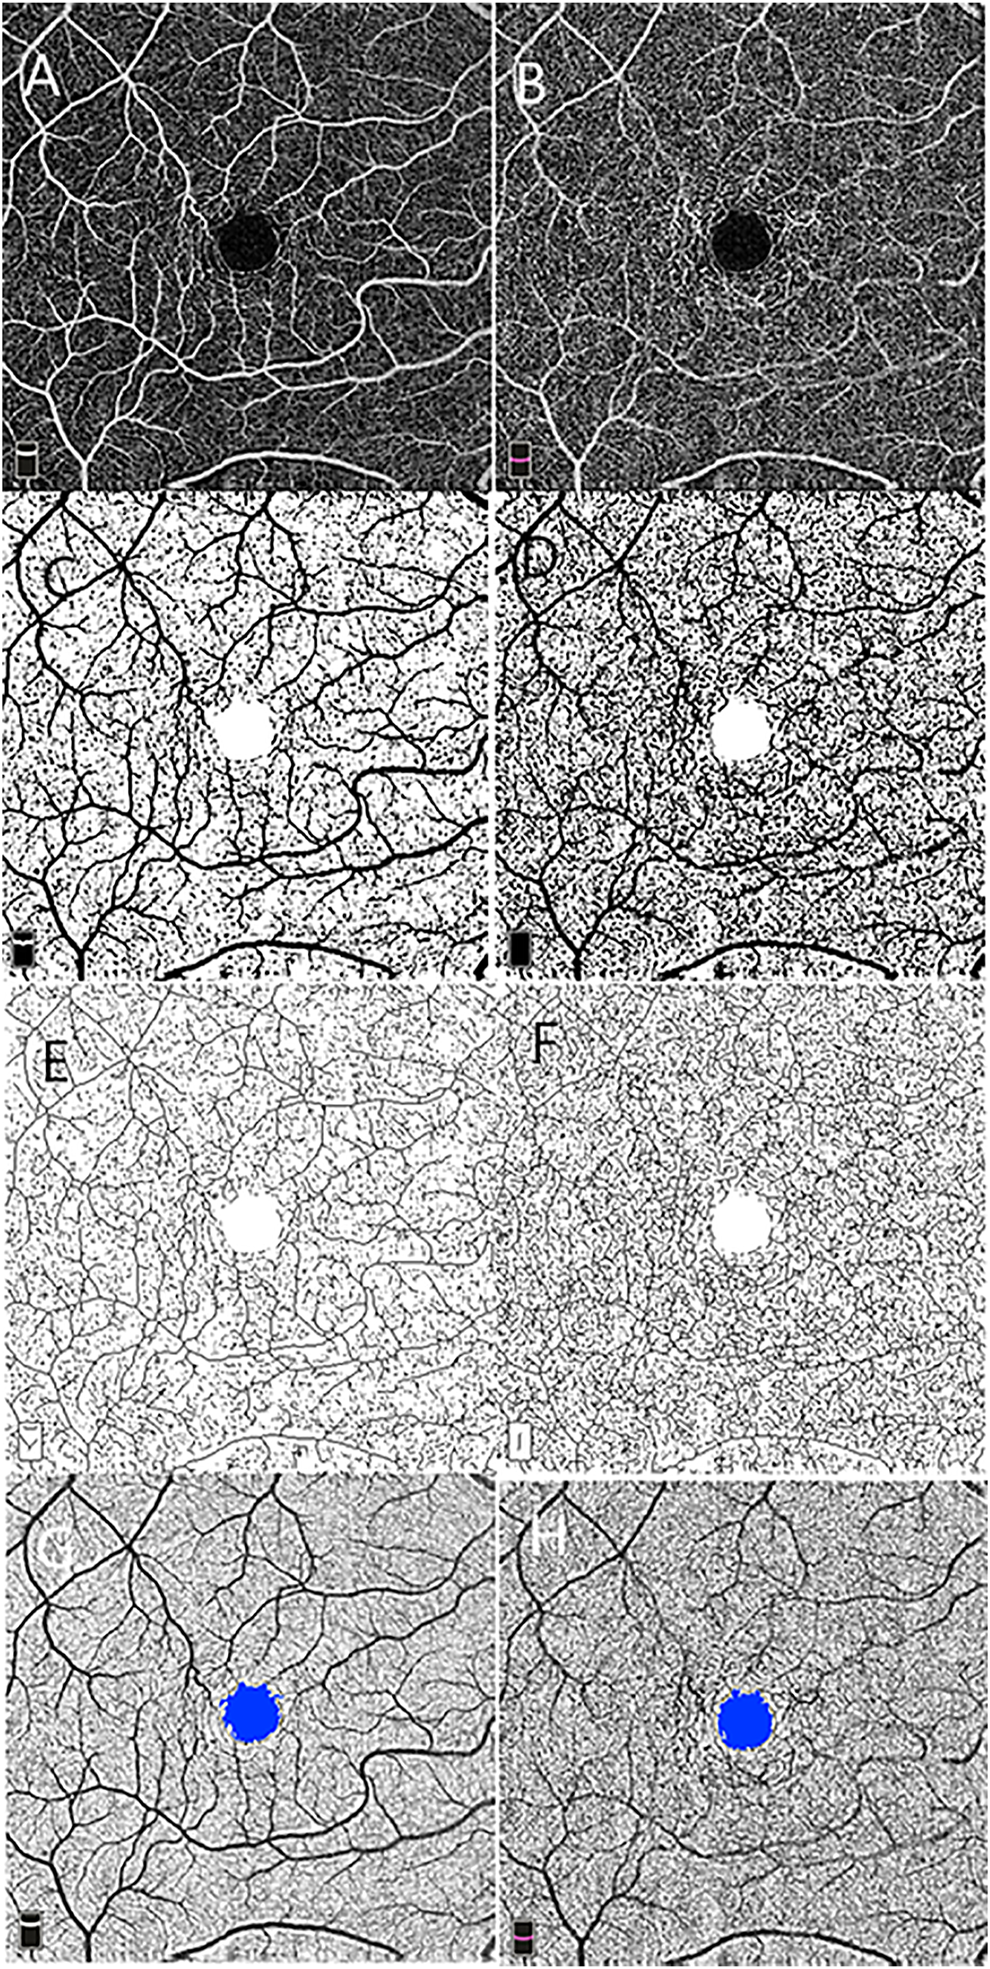

Macular scans (6 × 6 mm) centered at the fovea were obtained for each subject. Optical coherence tomography angiography images of superficial and deep capillary networks were generated separately using the automated software algorithm (Figures 1A,B). Based on these default settings, the superficial retinal layer (SRL) extended from 3 μm below the internal limiting membrane (ILM) to 15 μm below the inner plexiform layer (IPL). The deep retinal layer (DRL) extended from 15 to 70 μm below the IPL. The segmentations of all examinations were checked before any measurement was performed.

FIGURE 1

Macular vascular density measurement and foveal avascular zone (FAZ) analysis using 6 × 6 mm optical coherence tomography angiography scan centered on the macula at the level of the superficial (A) and deep (B) retinal vascular networks. Vascular density is measured in the entire contrast-enhanced binarized images of the superficial (C) and deep (D) retinal vascular layer. Skeleton density is calculated in the skeletonized images of the superficial (E) and deep (F) networks. The FAZ is shown on the superficial (G) and deep (H) networks.

Image processing and fractal analysis were conducted as described in a previous study. In brief, grayscale OCTA images of the superficial and deep capillary plexus were standardized, cropped, and binarized using a custom ImageJ macro (Zahid et al., 2016). One form represents binarization of the original scan obtained, allowing for measurement of VD (Figures 1C,D), which were calculated on the binarized images as a ratio of the area occupied by the vessel in the entire en face scan for superficial and deep networks subtracting the FAZ area. The second binary form is obtained by skeletonizing the acquired scan into 1-pixel-wide vessels allowing for measurement of SD (Figures 1E,F). SD is calculated by measuring the total vessel length in the obtained image. The VDI was calculated by using the binary blood vessel image and the skeleton image to yield the average vessel caliber in the OCTA image (pixels).

Fractal dimension (FD) as a measure of branching complexity was analyzed using the box-counting method with Fractalyse (ThéMA, Besancon Cedex, France). The box-counting method consists of dividing an image into square boxes of equal sizes and counting the number of boxes containing a vessel segment. Higher FD values reflect denser vascular branching patterns.

Foveal Avascular Zone Measurement

Using the acquired images, the FAZ area was defined as the area inside the central border of the capillary network at the level of the superficial and deep vascular networks (Figures 1G,H).